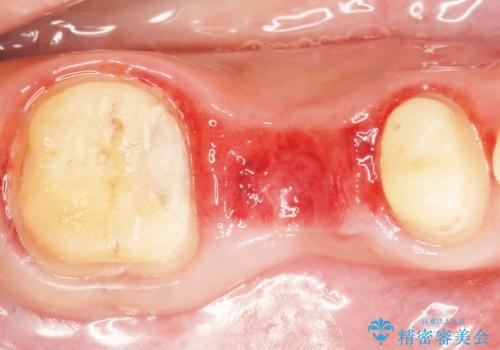

保存不可能な歯を抜去し、オールセラミックのブリッジによる補綴治療を行いました。

自然な仕上がりと咬み心地に喜んで頂けました。

「予算を抑えてしっかりとした治療が受けられた」とご満足頂けました。

プラークコントロール不良につき仮歯を精密に合わせても歯肉の腫脹を認めたため、工夫を凝らして精密な型取りを行うことで適合の良いクラウンを製作致しました。

クラウンの種類:ベレッツァクラウン